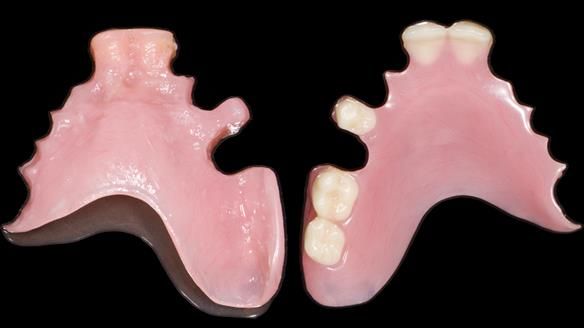

We provided her with an immediate upper denture (Mk 1), followed by a definitive metal-based upper denture (Mk 2). A lower removable partial denture was discussed, to be made only if needed once the upper treatment was complete. However, at review, this wasn’t necessary — Adnana had excellent neuromuscular control and function, even with a shortened dental arch (SDA).

Rowan, Sam Hesketh and Chris Hesketh provided the stunning technical work. I am very lucky to have them.